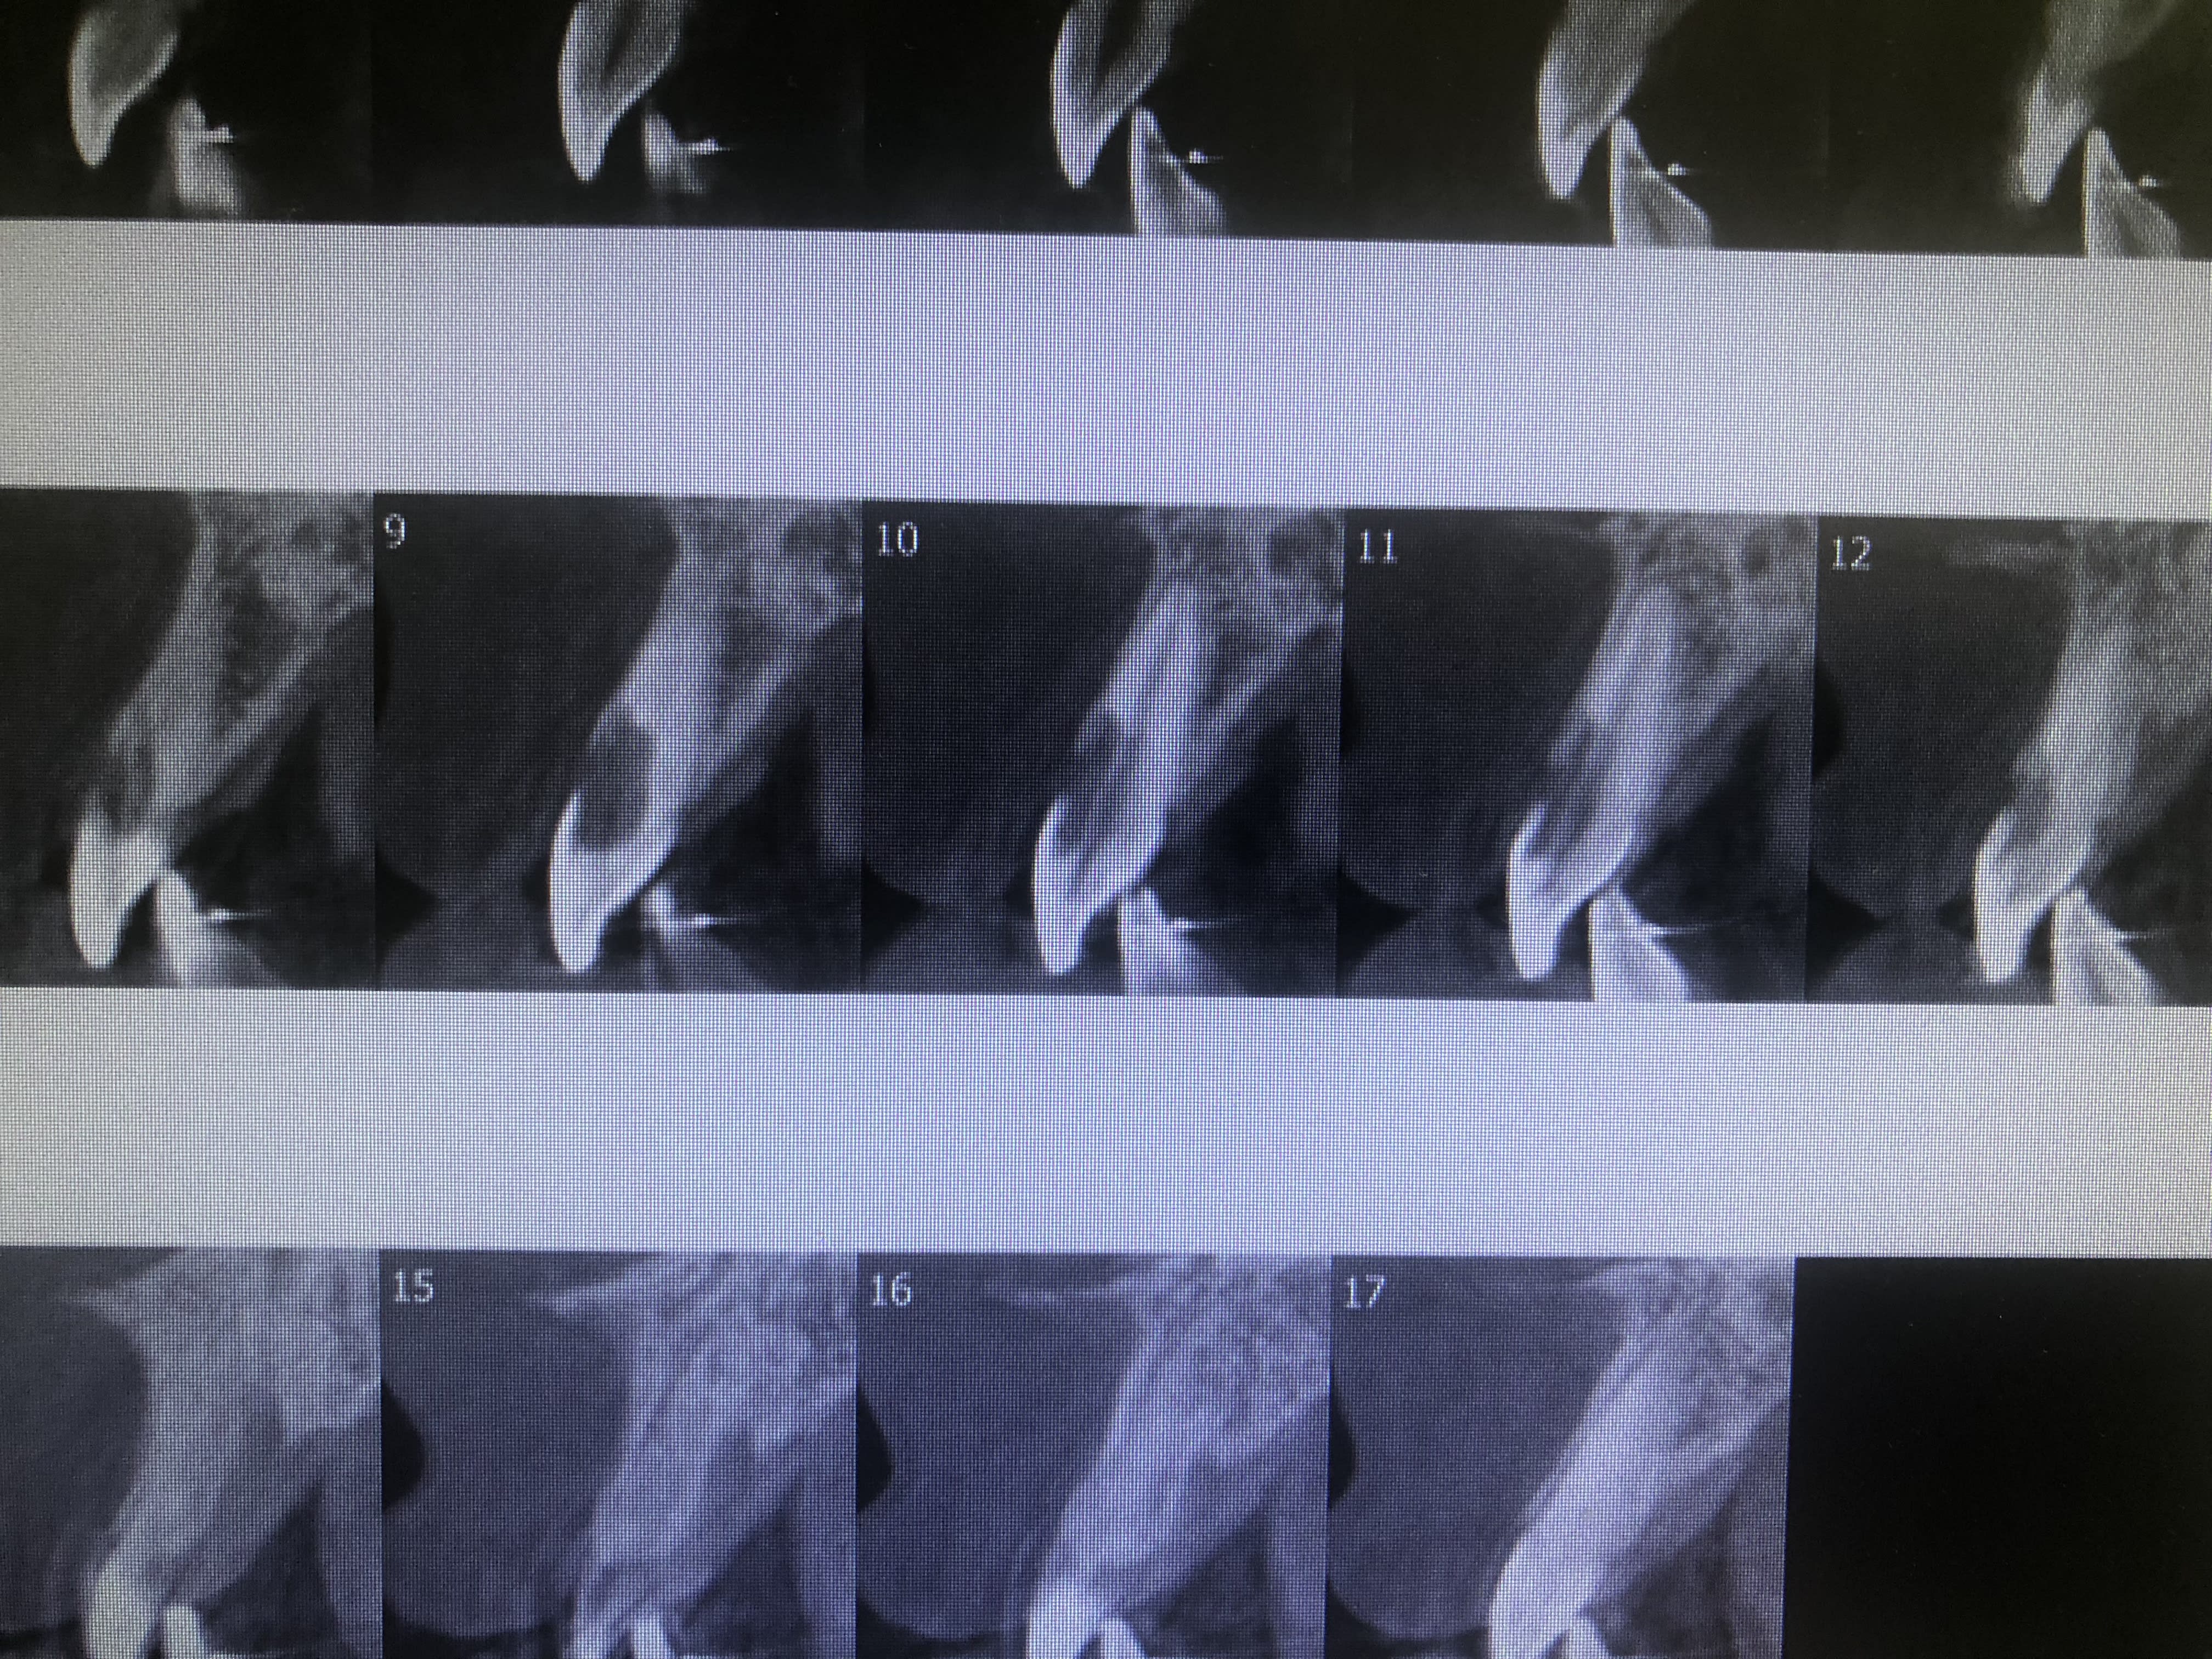

J’avais promis le cône beam...

348b1f60 e915 47be 8433 b4c70b503f8a vmixfc - Eugenol

Donc dans ton cas je confirme donc ce que j’avais dit :

1) on prolonge la position de la dent sur l’arcade : désinfection puis cône en place , on lève un lambeau on traite la lésion et obturation à la biodentine de la perforation , puis plus tard on enlève le cône on re désinfecte , obturation « définitive », compo en obturation palatine.

2) extraction implantation immédiate plus tard plus poudre de perlimpinpin

Quoique y a pas beaucoup d’os en vestibulaire. :)) à voir lors de l’extraction. :)

Des résorptions avec perforation comme ça c’est rare. Bon j’avoue t’as joué la carte de la sécurité. Mais avoue que sur le papier c’est tentant :)